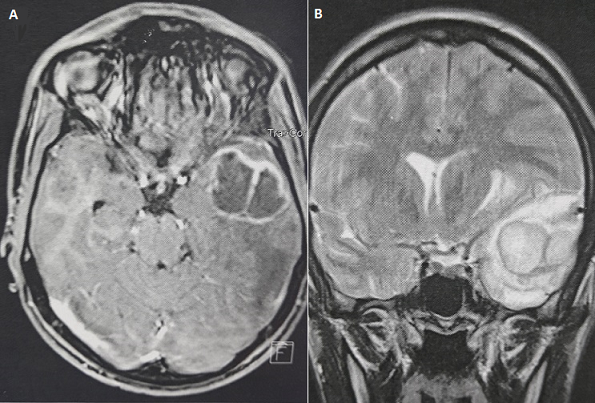

Un patient de 19 ans, sans antécédents particuliers, admis pour des crises convulsives généralisées depuis un mois. L'examen clinique initial était sans particularités. L'IRM cérébraux a objectivé deux lésions temporales gauches intra axiales à double composante kystique et charnue avec prise de contraste intense en périphérie. Le patient a bénéficié d'une exérèse tumorale à visée diagnostique et thérapeutique. L'examen anatomopathologique a posé le diagnostic d'une histiocytose cérébrale. Le bilan d'extension de la maladie comportant notamment une scintigraphie osseuse, un scanner thoraco-abdomino-pelvien était sans particularité. L'histiocytose langerhansienne est une pathologie à développement multi viscéral potentiel liée à la prolifération et à l'accumulation au sein de certains tissus de cellules de langerhans. Son diagnostic est anatomopathologique reposant sur la mise en évidence par immun histochimie de l'expression cellulaire de la protéine S100 et l'antigène CD1a, et la présence de granules de Birbeck en microscopie électronique. Cette pathologie atteint préférentiellement l'os, la peau, les poumons, le foie ou encore le sang. La localisation cérébrale reste exceptionnelle.